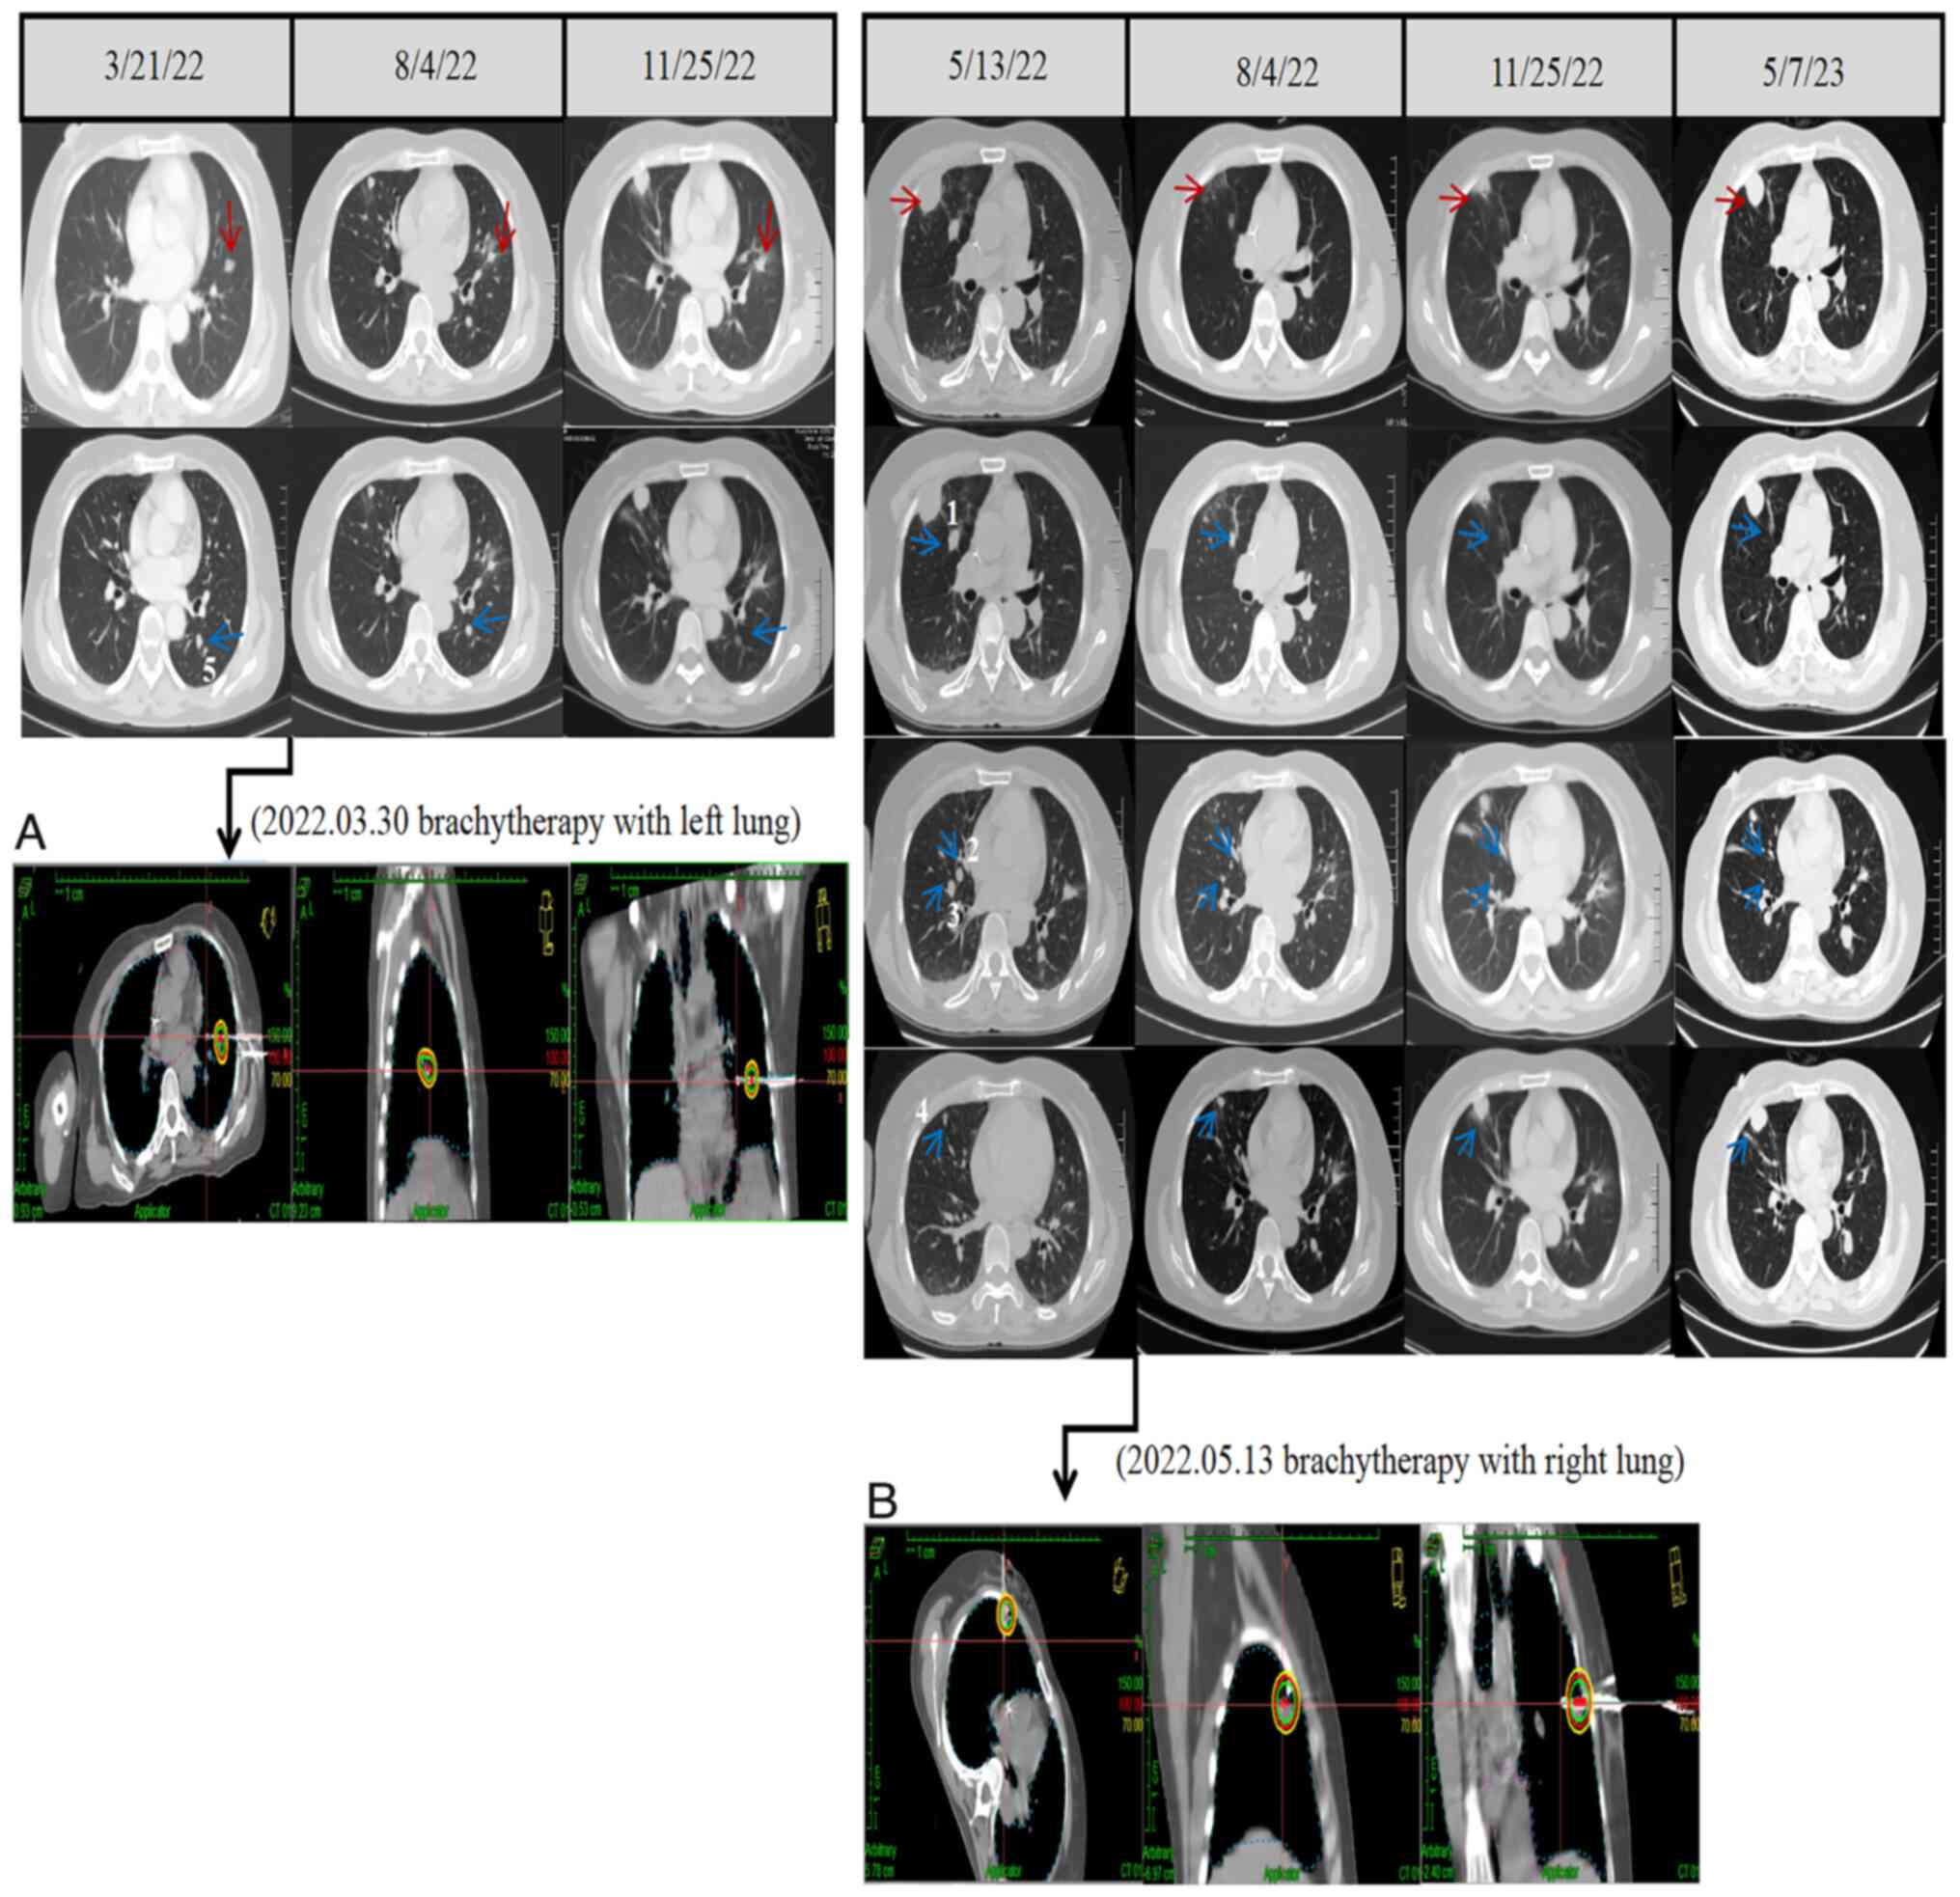

However, in January 2022, the patient consulted the Oncology Department of the Affiliated Hospital of Southwest Medical University (Luzhou, China) due to the persistent progression of the inguinal mass with pain and discomfort. PET/CT showed a soft tissue mass with increased glucose metabolism in the left inguinal region (diameter of ~48.9 mm) with a maximum standardized uptake value (SUVmax) of 17.5 (Fig. 2A). Multiple nodules were present in both lungs (the largest metastasis in the left lung tumor was 10.5 mm, and the largest in the right lung tumor was ~12.2 mm with a SUVmax of 2.9). After evaluation of the patient's condition in the Oncology Department, the patient underwent intensity-modulated radiation therapy for the left inguinal metastasis (3,414 cGy/7F) (Fig. 2B). Following radiotherapy for the left inguinal metastasis, the patient was treated with four cycles of pembrolizumab (200 mg, d0) and dacarbazine (385 mg, d1–5 po). During this period, owing to the increased and persistent lung metastases, the patient received single-fraction high-dose-rate brachytherapy, with a treatment dose of 49 Gy for the left lung metastases [D90 244 Gy by equivalent dose in 2-Gy fractions (EQD2)] (Fig. 3A) in March 2022 and 52 Gy for the right subpleural metastases (D90 269 Gy by EQD2) (Fig. 3B) 2 months later.

Figure 3.

Treatment and images of the lung tumors. (A) CT simulation images of the left lung radiotherapy planning. (B) CT simulation images of the right lung radiotherapy planning. The red arrows indicate the target lesions for the radiotherapy and the blue arrows indicate the observation lesions receiving lower dose scattering from nearby high-dose irradiation areas. 1–5 in the image represent the five observation lesions in the lung.

After the lung metastatic lesion was treated with single-fraction high-dose-rate brachytherapy, the time of lung radiotherapy lesion (target lesion) control was 8 months (Fig. 3). The observation lesions (observation lesions 1, 2, 3 and 5) adjacent to the target lesion received lower doses of scattering (0.9–1.8 Gy), and the time of lung observation lesion control was 9 months (except for observation lesion 4 in the right lung, which received a radiation dose of 7.8 Gy) (Figs. 3 and S1). After receiving HFRT for the left inguinal mass after immunotherapy, the radiotherapy target area continued to shrink, with a gradual relief of pain and discomfort and a significant improvement in the quality of life of the patient. In February 2023, an MRI showed no enlargement of multiple small lymph nodes in the bilateral inguinal area. The inguinal mass had largely disappeared, and the inguinal mass was assessed as complete response (CR; 100% regression of the lesion with no new lesions is considered CR) to treatment. After 2 months, the examination showed that the left inguinal mass was still under control (Fig. 2A), and the inguinal mass was still assessed as CR. The inguinal mass remained rated as CR until the death of the patient. The clinical history of the patient and the course of treatment are summarized in Fig. 4.

In addition, the observation lesions adjacent to the target lesions received lower doses of scatter from the HFRT of the target lesion (0.9–1.8 Gy), and most of the observation lesions (observation lesions 1, 2, 3 and 5) were sustainedly controlled [except for one observation lesion (lesion 4) in the right lung, which received 7.8 Gy. It was considered that the sustained remission of the observation lesions receiving low-dose scattering was attributed to the activation of immune cells by low-dose scattering, which regulated the microenvironment and thus regulated immunotherapy. In a study by Sezen et al (30), a 73-year-old female patient with metastatic vaginal mucosal melanoma received treatment with ibritumomab and nivolumab. In the liver, a second metastatic lesion received lower doses of scattering from the adjacent first metastatic lesion (received HFRT). The second metastatic lesion disappeared after 24 months, which was very similar to the present study. At present, the choice of HFRT and segmentation modality remains inconclusive. In the present case, the low-dose scatter of 0.9–1.8 Gy showed a relatively good effect for the observation lesions (observation lesions 1, 2, 3 and 5), whereas a radiation dose of 7.8 Gy was ineffective for observation lesion 4, which may be attributed to the fact that the lesion received low-dose scattering.